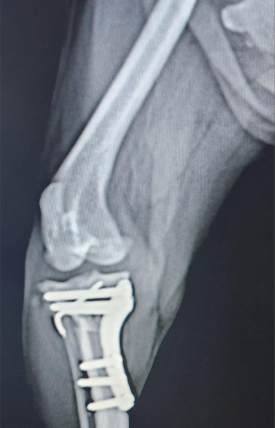

TPLO : Tibial Plateau Leveling Osteotomy

강아지 후지파행의 한 원인인 전십자인대 단열의 경우에 시행하는 수술로서 최근 낭외재건술보다 우선 선택되는 수술법입니다.